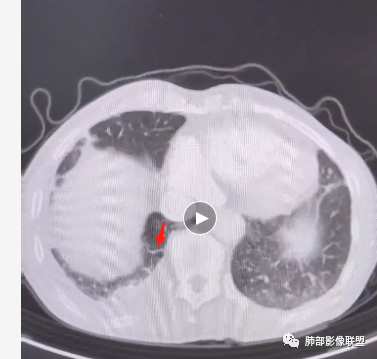

周围区域连续些看,感觉有树芽征。

Coke with ice:

如果这个树芽征明确的话,这个就不是肺水肿。可以做个最大密度投影或多方位观察再次确定是否有树芽征。弥漫性中轴间质和周围间质增厚常规就两个疾病谱,癌淋或肺水肿。而且这个人有明确的右肺明显。结合可疑树芽征,很多可以看到沿着肺动脉走形的磨玻璃影,需要可疑血源播散性转移或血管源性恶性肿瘤病变,再就是嗜血管的淋巴源性的恶性肿瘤。血管肉瘤,血管内淋巴瘤病可以这个表现,之前还碰见过一个,好像是NK/T淋巴瘤也这个表现,这个有点记不清了。

如果是肿瘤的话,右下肺这一坨怎么解释呢,看着确实是增粗的肺动脉。

2.右肺广泛密度增高、腺泡结节样磨玻璃影,血管影明显扩张,小叶间隔增厚。

(5)可合并肺梗死,表现为肺外周胸膜下密度均匀的楔形病灶,尖端指向肺门。可出现反晕征及空洞等。